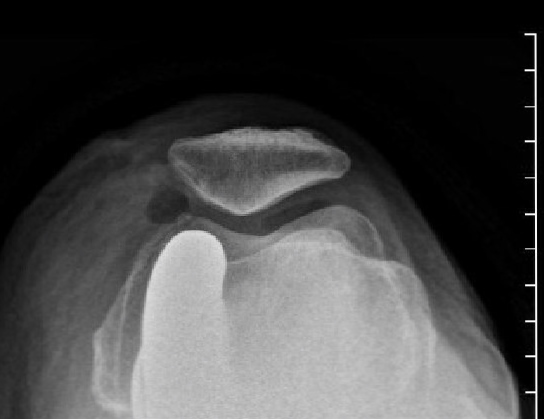

These are the x-rays with the implants in: